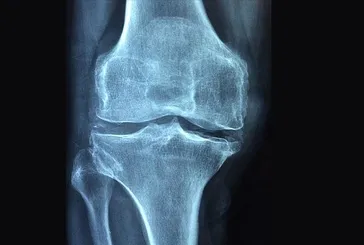

Hareket et osteoporozu geç

Hareket et osteoporozu geç Osteoporoz yani kemik erimesi, daha çok kadınlarda görülüyor. Özellikle menopozdan sonra artış gösteriyor. Doç. Dr. Ahmet İnanır, “Hareketsizlik tetikliyor. Düzenli spor yapın” diyor.

Kemik erimesi yaşa bakmaz!

Kemik erimesi yaşa bakmaz! Kemik erimesi, hayat kalitesini düşürüyor. Doç. Dr. Hakan Sofu, genellikle yaşlılarda meydana gelen hastalığın gençlerde de görüldüğünü söylüyor.

Kemik erimesi ailenizin eseri

Kemik erimesi ailenizin eseri Sırt ağrısı ve kırıklara yol açan kemik erimesi, yaşam kalitesini düşürüyor. Daha çok kadınları tehdit ediyor. Uzmanlar uyarıyor: Ailesinde bu hastalık olanlar kontrolleri aksatmasın.